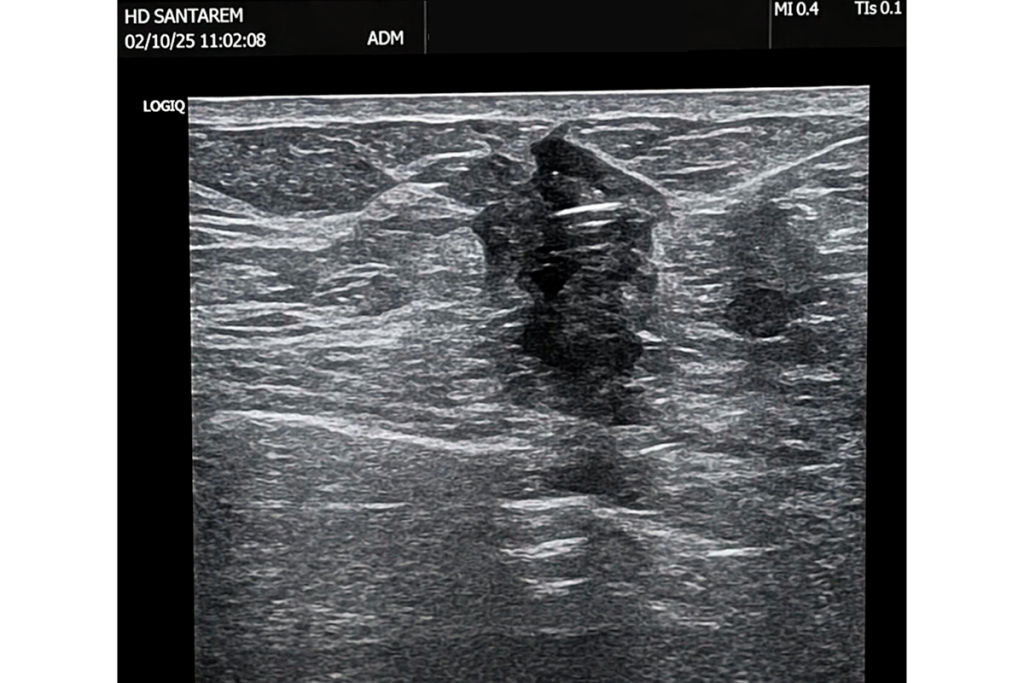

A inovação está a ser aplicada na Unidade de Patologia Mamária, onde a ecografia intraoperatória é utilizada de forma sistemática como método de orientação cirúrgica. Desde outubro de 2025, este procedimento passou a ser complementado por um sistema de marcação assistida por tecnologia Sirius, especialmente indicado para lesões ultrapequenas, cuja visualização por ecografia pode ser limitada.

Segundo explica Madalena Nogueira, coordenadora da Unidade de Patologia Mamária, “o processo inicia‑se com a intervenção do médico radiologista, que identifica a lesão por técnicas de imagem e procede à colocação de um marcador no interior do tumor. Posteriormente, em contexto de bloco operatório, o cirurgião de mama recorre ao sistema Sirius, que permite detetar o marcador com elevada precisão e localizar em tempo real o ponto exato da lesão”.